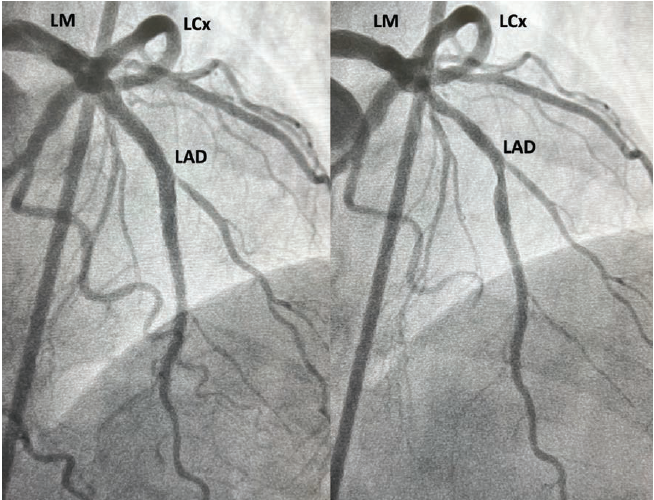

We planned on using the OPN NC super high-pressure balloon (SIS Medical AG) to expand the under-expanded stents. We attempted to perform optical coherence tomography (OCT) (Abbott Cardiovascular) of the LAD, but were unable to cross the more proximal area of stent under-expansion in the mid LAD (Figure 1, Letter A) with the OCT catheter. Next, we attempted pre-dilating, but despite a 7-French (F) extra backup 3.5 guide catheter, 7F guide extension catheter, and extra support guidewire, no balloon could be delivered across that lesion. We therefore performed laser atherectomy with an 0.9 mm laser (Philips) at 80 fluence and 80 pulses per second for a total treatment time of 180 seconds, facilitated by concomitant administration of 70% contrast to cross the proximal and mid lesions (Figure 1, Letters A and B). After laser atherectomy, we pre-dilated the LAD with a 2.5 mm x 20 mm semi-compliant balloon up to 20 atmospheres (atm). OCT of the LAD was performed, which despite pre-dilation, showed a minimal stent area (MSA) of 1.19 mm2 (Figure 2). We attempted to expand the lesion with a 2.5 mm x 12 mm noncompliant (NC) balloon at 22 atm, but this showed a significant waist (Figure 3). Dilation with a 3.0 mm x 10 mm OPN NC super high-pressure balloon at 35 atm, however, resulted in complete expansion of the under-expanded segment of stents (Figure 3). The remainder of the LAD was post-dilated with 4.0 mm and 3.5 mm NC balloons up to 20 atm. OCT was performed again, showing good stent expansion and an improvement in the stent area at the more distal lesion from 1.19 mm2 to 4.50 mm2 (Figure 2). Final angiography also showed a significant improvement in expansion of the LAD stents (Figure 4).